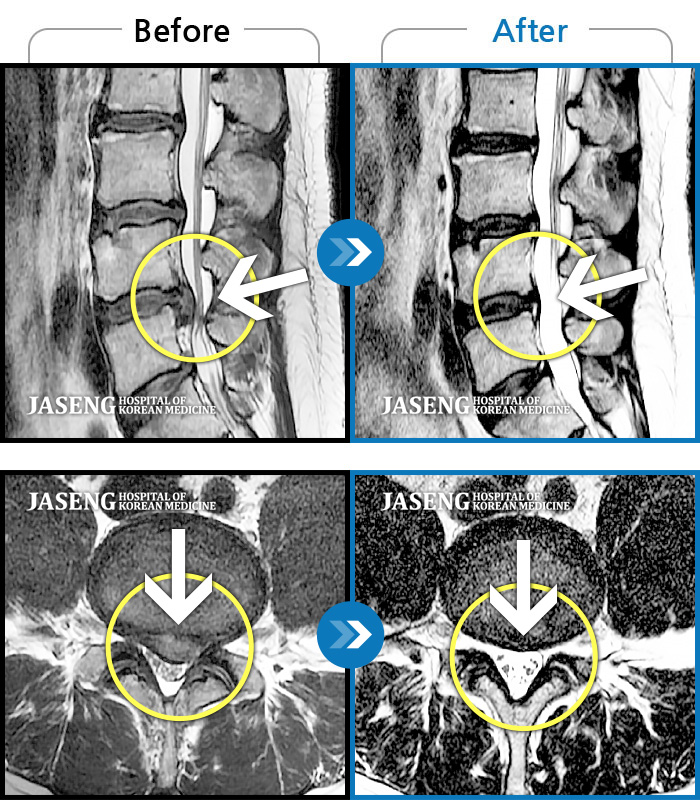

MRI ũ ʸ Ȯϼ.

[ؿ] 24.10.10~25.04.23